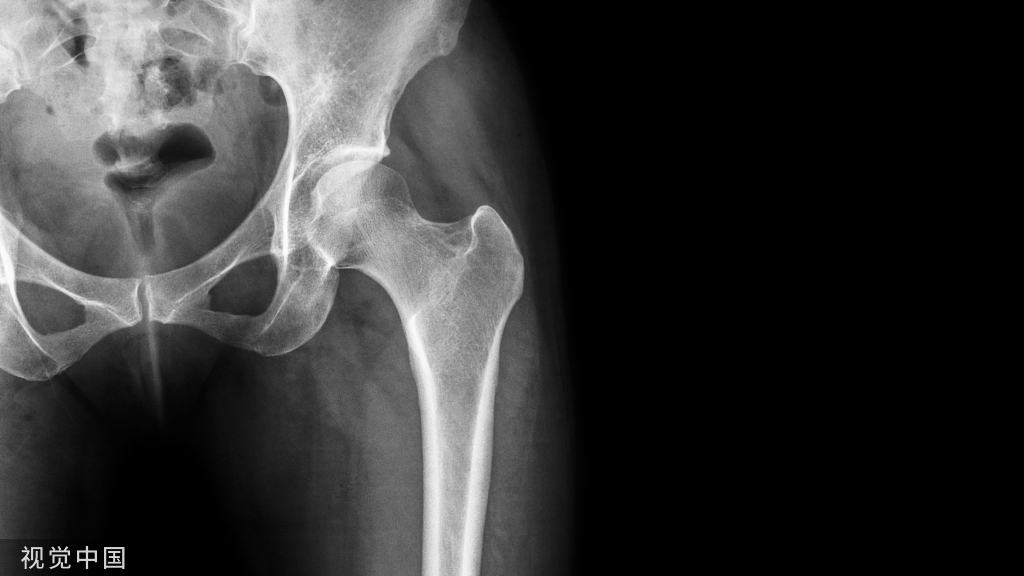

骨折几乎总是与某种程度的软组织损伤有关。虽然外科医生无法改变初始损伤造成的损伤程度,但他们可以通过熟练使用器械和牵开器,避免对这些受创组织造成进一步损伤。相反,在寻求实现骨折的解剖修复时,外科医生往往忽视了骨折广泛暴露造成的医源性损伤。更常见的是,手术助手因粗心应用牵开器而对组织造成进一步伤害。然而,在没有骨折的情况下也可能发生广泛的软组织损伤,不正确的处理最终会导致功能障碍。